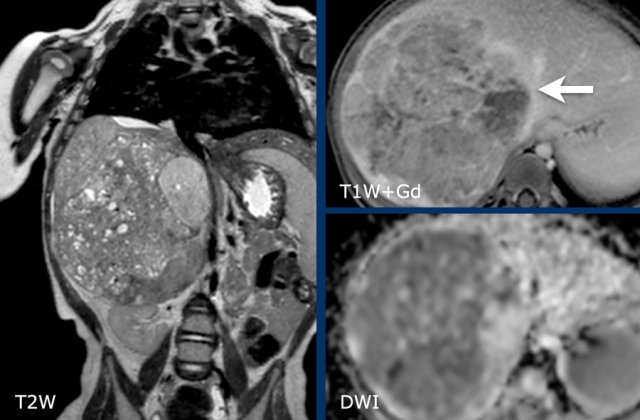

MRI shows a solid hepatic mass with multiple small cysts.

After contrast injection the mass is seen to be limited to the right posterior and anterior section, bordered by the middle hepatic vein (arrow).

The mass has moderate diffusion restriction.

Biopsy was compatible with an epithelial hepatoblastoma.